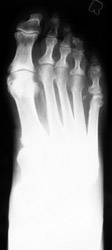

Ankylosing Spondylitis: Erosions of 5th MT headAnkylosing Spondylitis: Lateral- Broad base calcaneal spur and erosion of the calcaneusAnkylosing spondylitis (AS) is a HLA-B27 spondyloarthropathies which is characterized by bony ankylosis and syndesmophyte formation.

Erosion pattern:

Erosions are usually superficial, with productive response. Intra-articular ankylosis occurs in a short period of time.